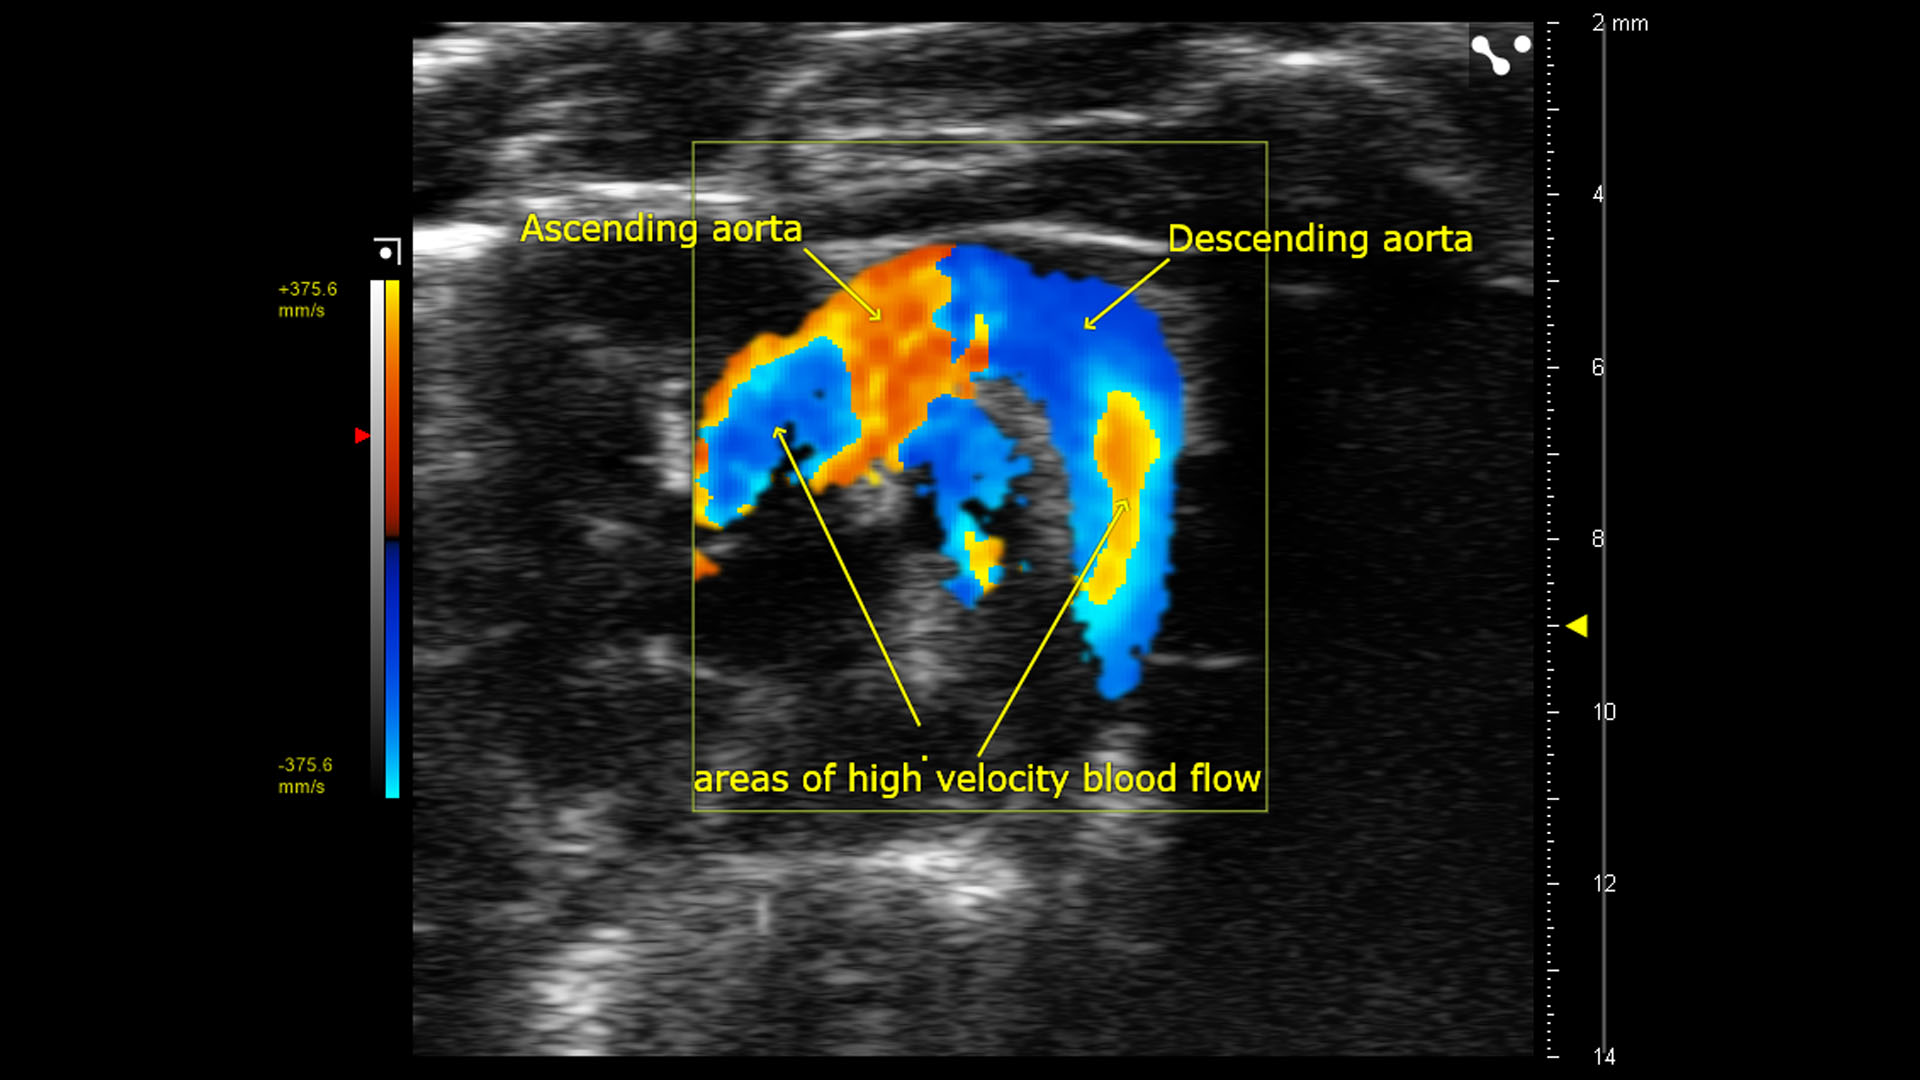

From www.visualsonics.com

Color Doppler of Mouse Aortic Arch FUJIFILM VisualSonics Mouse Echocardiography Machine The rodent cardiovascular phenotyping core provides echocardiographic services to assess cardiovascular function in mouse models and to. In the last two decades, it has been the most frequently used technique to assess left ventricular (lv) structure and function. Cardiac ultrasound is a challenge for most ultrasound machines, but with two echocardiographers on team, it’s our favourite. The core offers echocardiography. Mouse Echocardiography Machine.